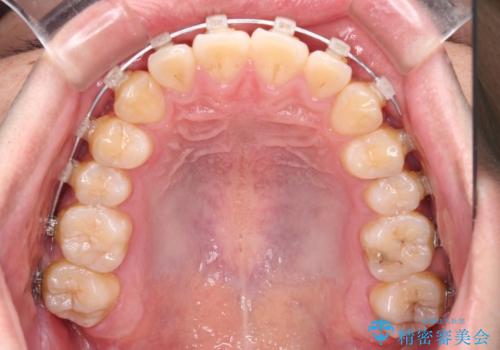

- クリアブラケット

- 治療期間

- 1年4ヶ月

治療開始の頃は、食事や歯磨きが慣れず、装置が頻繁に脱落しましたが、2,3ヶ月ほどで慣れ、その後は1年ほどで治療を終えることができました。